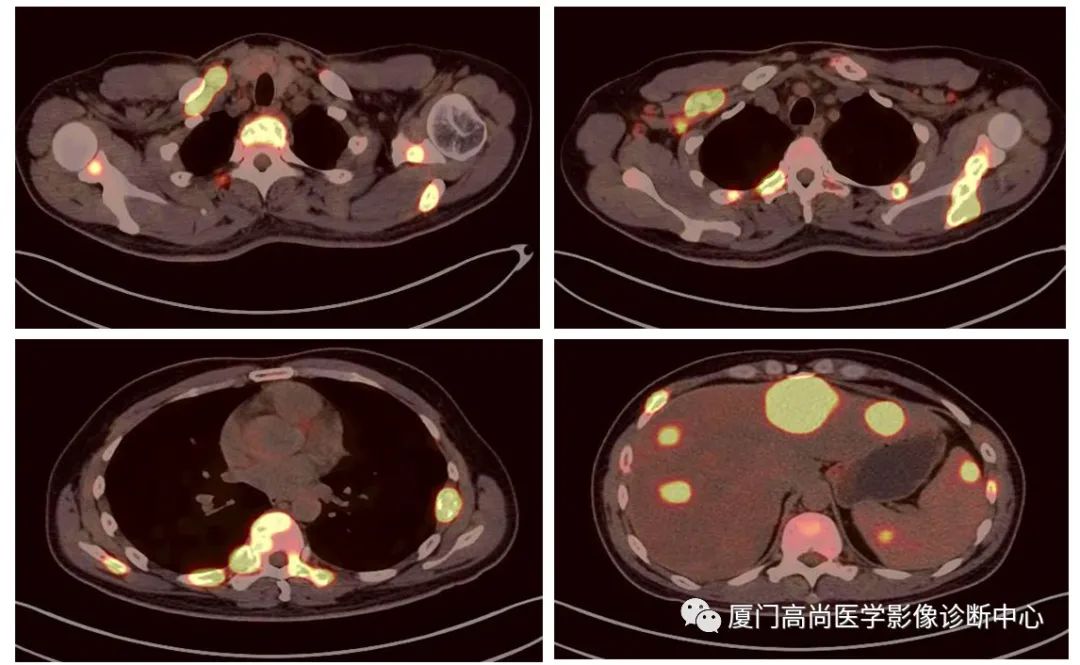

病例1:某男士,36歲,半年前摔傷,當(dāng)時無大礙,近幾個月來腰腿痛,并逐漸加重,消瘦10多斤。MRI檢查發(fā)現(xiàn)腰椎、骨盆 骨質(zhì)異常信號,查血各項腫瘤標(biāo)記物正常,因診斷不清而來做PET/CT檢查

淋巴瘤在骨骼、肝臟、脾臟、淋巴結(jié)表現(xiàn)

肝臟、脾臟、骨骼淋巴瘤病灶

骨骼、腋窩淋巴結(jié)病灶

PET/CT發(fā)現(xiàn) :全身多發(fā)淋巴結(jié)腫大,F(xiàn)DG攝取增高;肝臟、脾臟多發(fā)低密度結(jié)節(jié), FDG攝取增高;雙側(cè)扁桃體腫大,F(xiàn)DG攝取增高;全身多處骨骼破壞,F(xiàn)GD攝取增高;上述考慮為淋巴瘤

經(jīng)淋巴結(jié)穿刺活檢 :病理診斷為彌漫大B細胞淋巴瘤